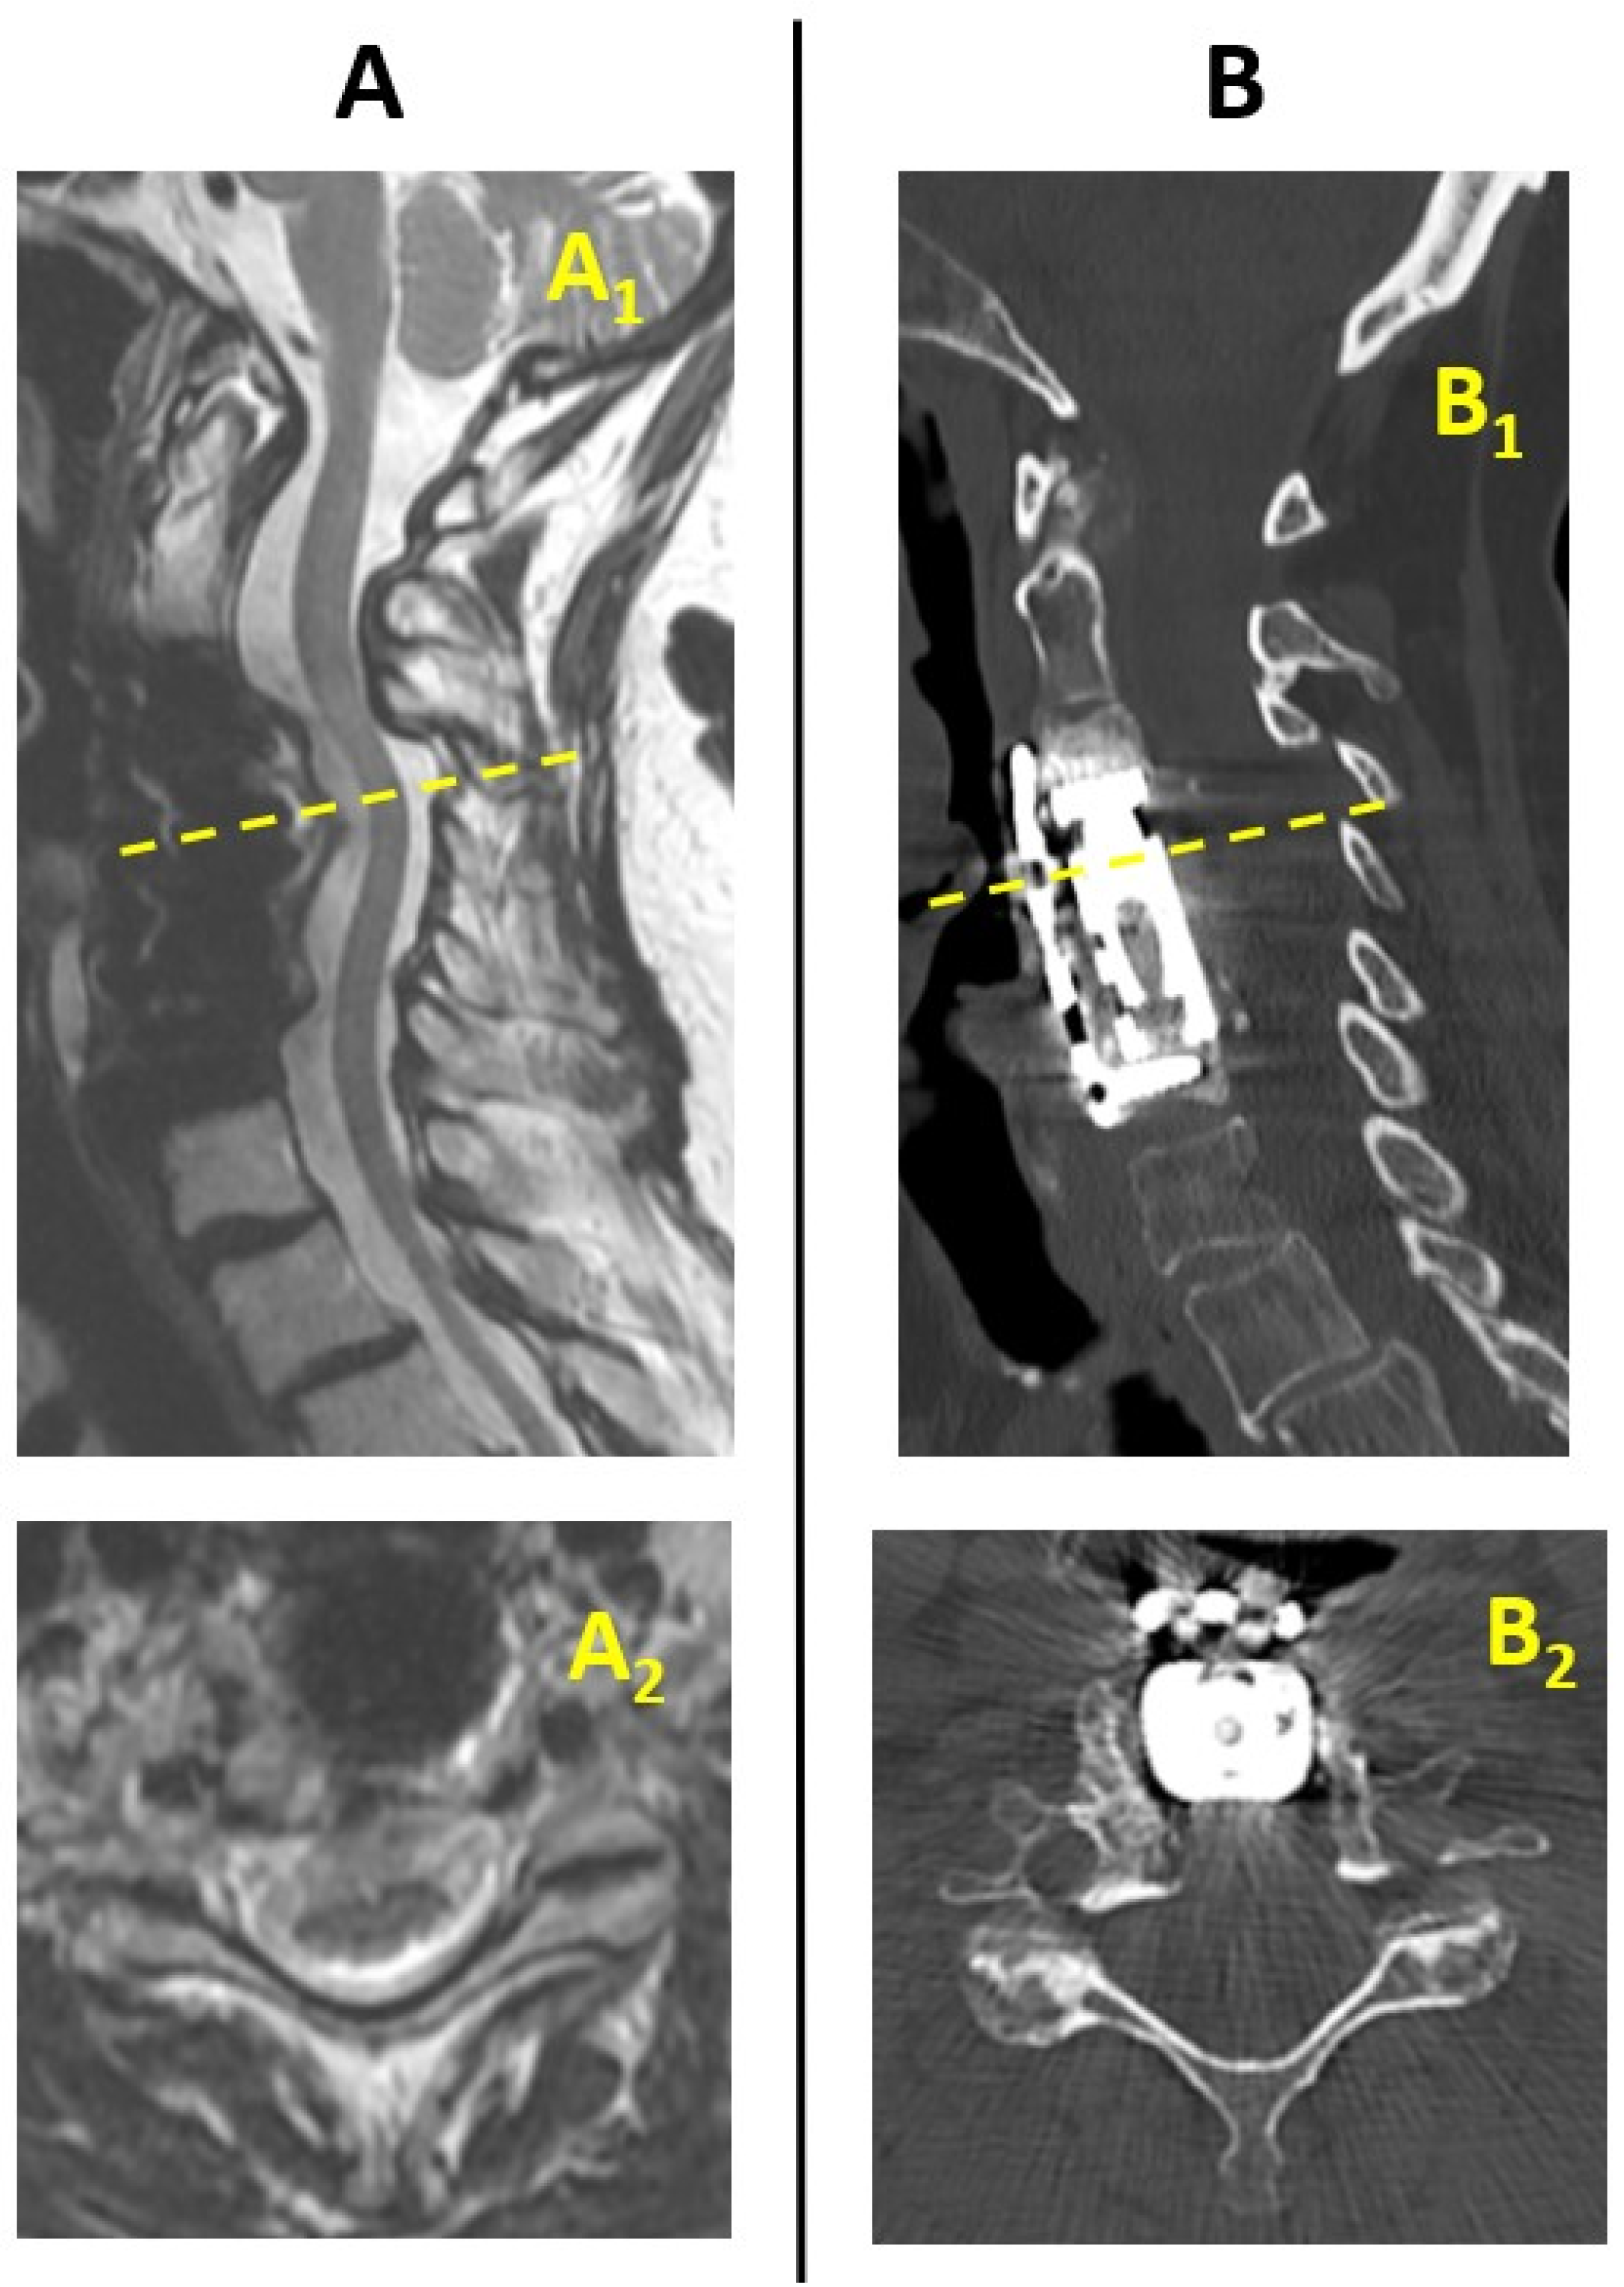

2. Case Report